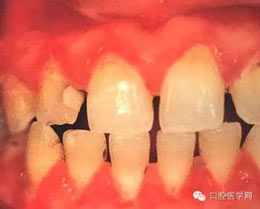

(五)牙周炎:為牙周軟組織喪失及不規(guī)則骨破壞,可有明顯的疼痛。(早期)牙周炎軟組織損害呈火山口樣。